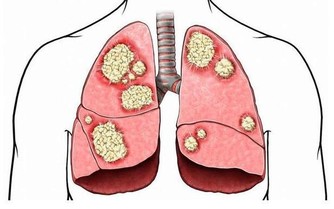

1.早期症狀(1-3年)

如果發現長輩有阿爾茨海默病的跡象,儘早到醫院確診。早發現早治療也能有效避免病情進一步加深。

• 短期記憶力下降,阿爾茨海默病早期患者的長期記憶通常不會受到影響,但短期記憶會變得模糊。老人可能會忘記你們剛剛的談話,也可能會重複問那些你已經回答的問題。

• 說話不清,組織語言的能力降低,說話經常忘詞,說話斷斷續續或邏輯混亂。

• 無法接受新事物,能做些已熟悉的日常工作,但對新的事物卻表現出理解困難。

• 情緒異常,情感反應淡漠,容易發脾氣或多疑。比如經常懷疑子女拿了她的衣服、錢或其它物品,由此可能會導致家庭爭吵,這時子女應該考慮患阿爾茨海默病的可能。

• 判斷能力下降,不能對事件進行分析、思考、判斷,處理複雜的問題較困難。

• 工作或家務勞動能力下降,不能獨立購物等,與人交往困難。

• 複雜結構的視空間能力差,不能準確辨別時間、地點和人物。可能會迷路。

• 衛生習慣變差,如果你發現,過去注重儀表、追求時尚的親友現在經常會忘記梳理頭髮甚至穿污損的衣服,請提高警惕並給予更多的關愛。